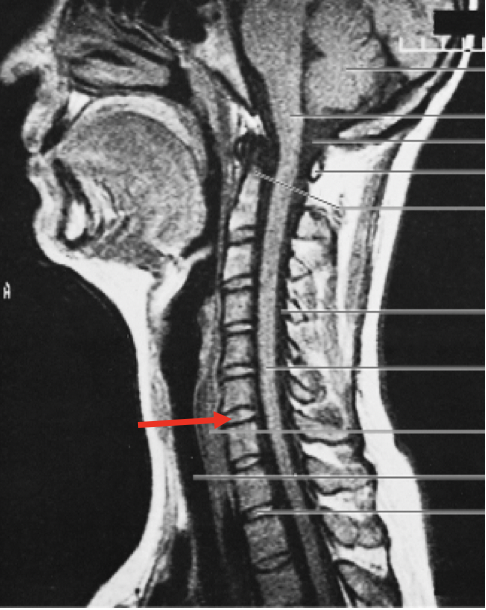

What is the red arrow pointing to?

the nucleus pulpous of the intervertebral disc